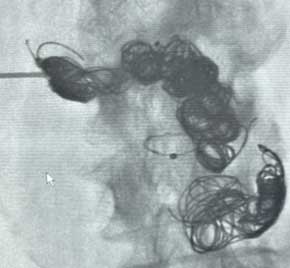

Embold Fibered Coils treatment of an AVM

Scan of vein before placement of coil. Visualizing the pulmonary artery​

Scan of vein after Embold fibered coil. After Embold Fibered placement​

Preston Eiswirth, MD​

Intermountain Medical Center​

Murray, UT​